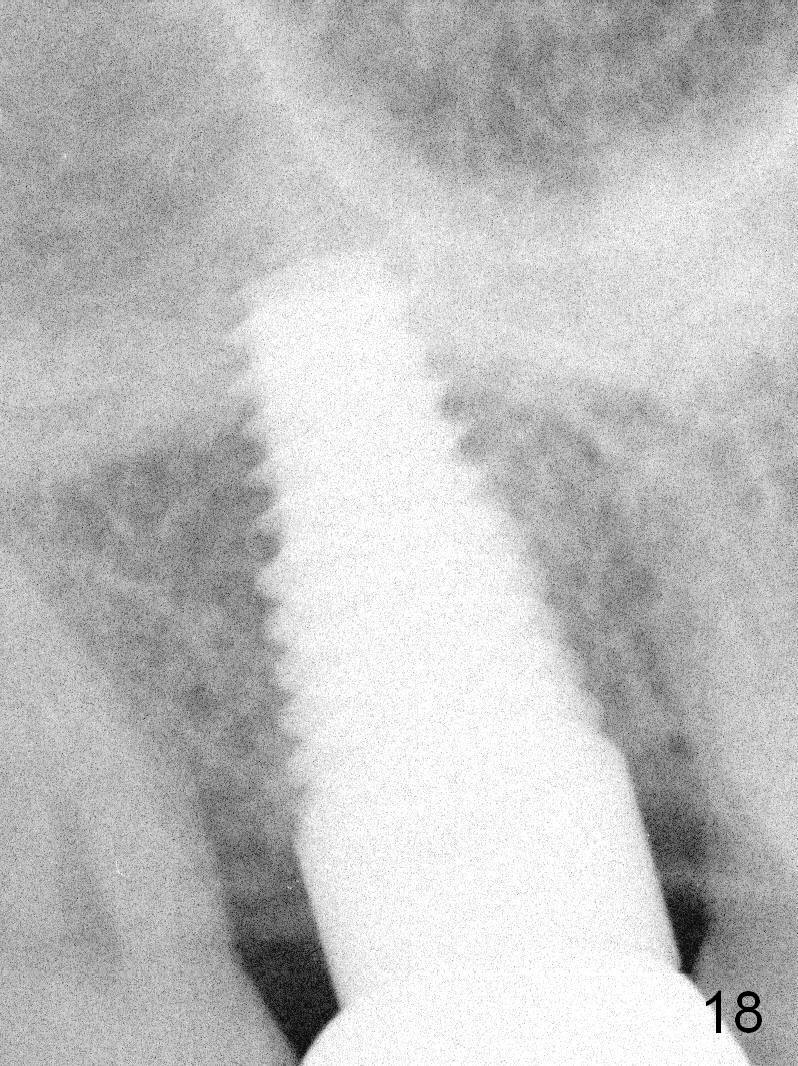

The patient returns for unknown pain on the right side 1.5 years post cementation (Fig.18,19). The gingiva is healthy. Two months later, the tooth #3 is found to have fractured.